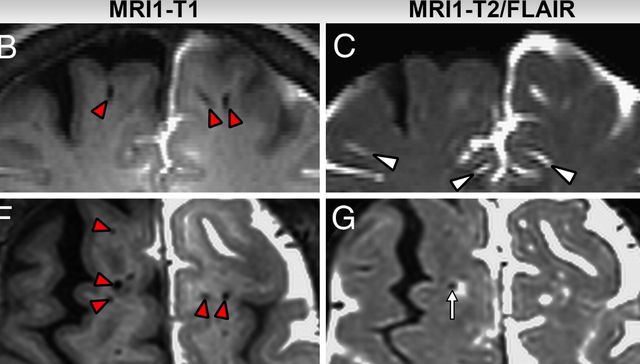

Muestran por primera vez las vías del cerebro para eliminar sus residuos